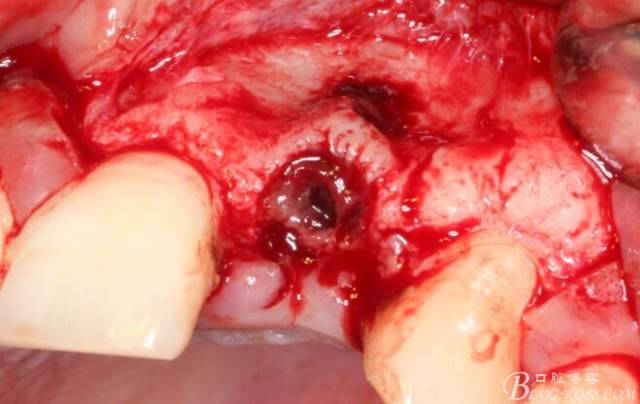

于是我果斷告知患者,手術(shù)失敗了,不能拖延,如不及時處理,炎癥繼續(xù)發(fā)展會很快波及鄰牙牙槽骨?;颊呓邮芪业慕ㄗh。切開翻瓣,骨粉及生物膜消失了,骨吸收嚴(yán)重,幸運的是,因為處理及時,鄰牙骨支持依然存在。

徹底掻刮。